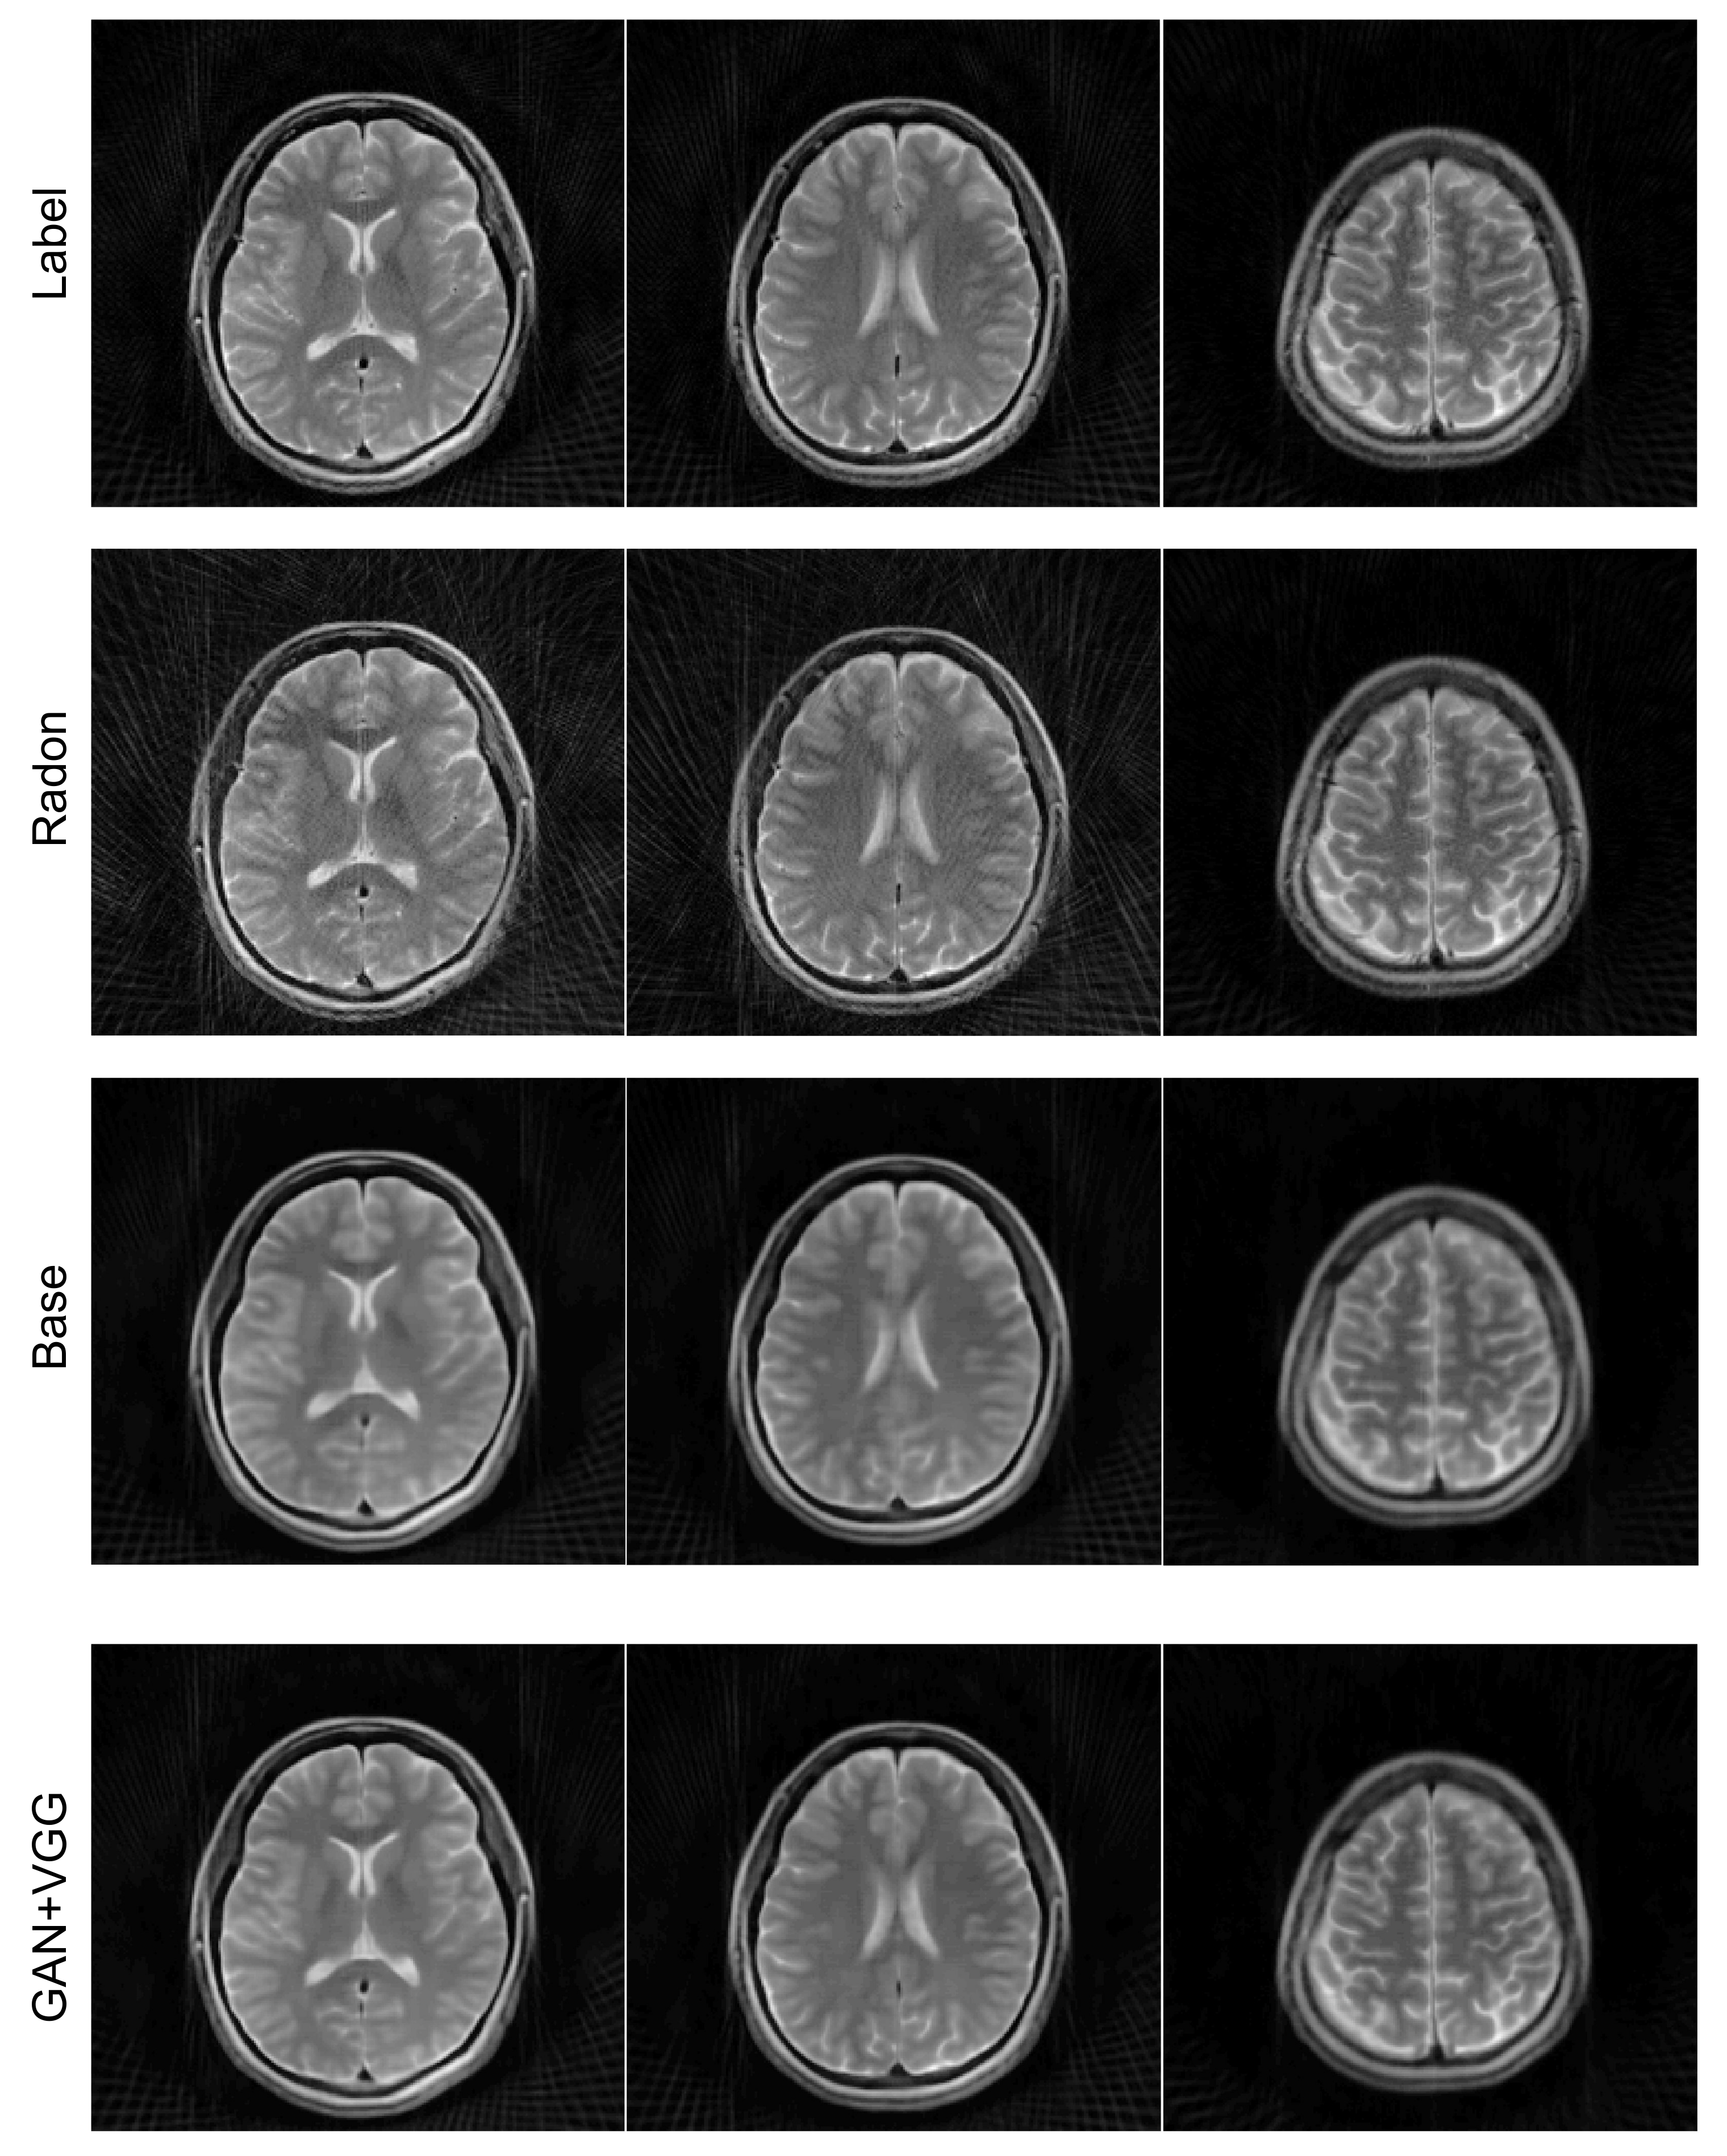

4.4. Radial Sampling Data

The reconstructed images from radially sampled k-space data are shown in Figure 9. When the filtered back projection was used to reconstruct the images from the undersampled radial k-space data, the streaking artifacts could be observed in the images, as shown in Figure 9 (rows 2). In contrast, the ETER-net provided improved image quality (rows 3 and 4). Moreover, the comparison of the images in rows 3 and 4 demonstrates that the loss function including Euclidean distance, adversarial loss, and perceptual loss improved the image quality. The improvement owing to the additional loss functions can also be validated by the quantitative measures in Table 1. The average nMSE is 3.51% for the filtered back projection, 1.98% for the proposed method with L1 loss only, and 1.49% for the proposed method with additional losses. In terms of SSIM, the average score of the filtered back projection is 0.786, the average score of the proposed method with L1 loss only is 0.922, and the average score of the proposed method with additional losses is 0.938. The proposed method with additional losses shows the least error and highest SSIM.

Figure 9.

Comparison of inverse Radon transform with the proposed method with/without additional losses. Four example images reconstructed from radial k-space data with 100 view angles are shown. Label: reconstructed images from radial k-space data with 400 view angles by inverse Radon transform, Radon: inverse Radon transform, Base: the proposed method with the baseline loss function, GAN + VGG: the proposed method with additional adversarial and perceptual losses.